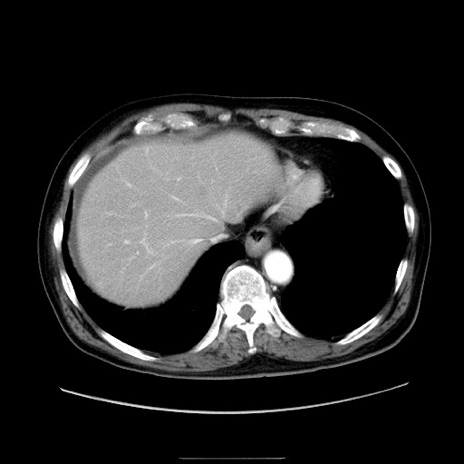

冠状断像

症例30(横断像)

【症例】80歳代男性

【現病歴】約6時間前から臍下部痛が出現。次第に腹部膨隆・背部痛も生じてきたため来院。背部痛の場所は変化しない。

【身体所見】意識清明、BT 36.3℃、BP  131/87mmHg、P 87bpm、SpO2 100%(RA)、臍周囲自発痛・圧痛あり、反跳痛なし、自発痛部位に一致して板状硬あり、腹部膨隆、腸雑音減弱、CVA tenderness両側陰性。